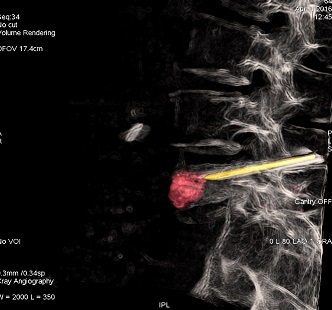

病例名称:IGS 3D在腰椎骨折介入中的应用

治疗后3D表现:

应用IGS 3D采集图像,并对3D重建图像进行后处理,不仅可以及时评估治疗效果,还可以即使调整治疗方案& #40;如进针方向或是评估填塞骨水泥的量是否足够& #41;,对临床治疗非常有意义。